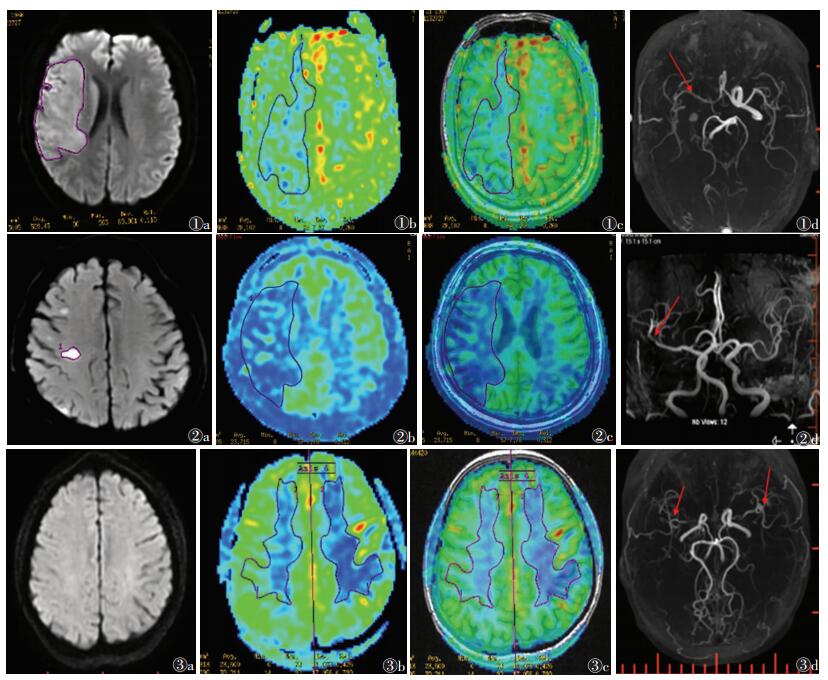

2 结果脑卒中19例(图 1,2),其中血管正常4例,颈内动脉狭窄、闭塞硬化4例,大脑前动脉狭窄2例,大脑中动脉狭窄闭塞9例。TIA 2例(图 3)。

| 图 1 男,64岁,急性脑卒中 图 1a DWI示右侧额顶叶斑片状高信号影 图 1b,1c 自旋标记技术-脑血流量图(ASL-CBF)及ASL与3D-T1匹配图像,ASL可见右侧额顶叶灌注较左侧明显减低 图 1d MRA示右侧大脑中动脉远段以及右侧前交通动脉局部血管血栓形成,管腔狭窄(箭头) 图 2 男,50岁,亚急性脑卒中 图 2a DWI示右侧侧脑室旁大片稍高信号影 图 2b,2c ASL-CBF及ASL与3D-T1匹配图像,ASL可见右侧半卵圆区较左侧灌注明显减低 图 2d MRA示右侧大脑中动脉管腔稍细,显影较左侧欠佳(箭头) 图 3 女,48岁,短暂性脑缺血发作 图 3a DWI未见异常表现 图 3b,3c ASL-CBF及ASL与3D-T1匹配图像,ASL示左侧额顶叶白质区灌注较右侧明显减低区 图 3d MRA可见左右侧大脑中动脉M1段血栓形成,管腔狭窄,周围多发小吻合血管(箭头) |

脑卒中病灶中心区的CBF平均值为(24.4±1.81)mL·(min·100 g)-1,对侧相应区的CBF平均值为(38.67±3.07)mL·(min·100 g)-1,差异有统计学意义(P=0.00)。其中17例ASL示病灶面积大于DWI,2例ASL显示病灶面积小于DWI(图 1,2)。